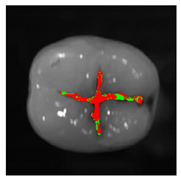

The classification model generated by the fine kNN algorithm was used to classify the fissural systems of five additional teeth, which were not included in the training and evaluation of the algorithm (Table 3). The projection maps show that the classified enamel state is in good agreement with the PLM images in the histologically validated area: Stained samples show a nearly homogeneous distribution of the predicted enamel state “stained”. However, some clearly circumscribed regions away from the histologically validated area are classified as “stained lesion”. Stained lesion samples exhibit a more heterogeneous distribution of enamel health states: A large proportion of fissural areas are classified as “stained lesion”; however, there are numerous “stained” regions of varying sizes dispersed in between.

Table 3.

Clinical simulation of enamel health predictions using HSI-based automated classification as a decision-support system. Five additional teeth (two stained [(a) and (b)], three stained lesion [(c) through (e)]) were imaged and classified by the previously trained fine kNN classification algorithm (i.e., the samples in this table were not included in algorithm training). Stained sound enamel is displayed green, whereas lesions (stained or unstained) are displayed red. Polarization microscopy images from each tooth’s sectional plane (dotted lines) serve as reference. All scale bars = 1 mm.

The results in this study are based on the simplified assumption of a homogeneous distribution of the occlusal health state that was histologically determined at the central region of the fissure. Occlusal caries originates from the fissure in the vast majority of cases. The part of the fissure that clinical experience showed to be the most questionable part (i.e., the most likely to be carious) was selected for further analysis in this study, as this is the clinically most relevant issue. As caries is a dynamic process, however, occlusal classification images show heterogeneous enamel health states (Table 3). Lesions may develop in one or more sites of the fissure and subsequently spread to further areas. Hence, it is likely that some parts of an analyzed tooth are still unaffected, whereas others contain lesions of varying extent. Thus, teeth showing sound but stained enamel in the histological cross-sectional plane may show lesions in other parts of their fissure (Table 3a,b). On the other hand, histologically carious teeth show still unaffected fissural regions (Table 3c,e). In order to refine the validation process, further cross-sections from different parts of the tooth’s fissural system should be considered. Occlusal caries originating from outside the fissure are rare and pose no pertinent clinical issue. In close proximity to the histologically validated areas, the HSI-based classification results show very good agreement with the reference occlusal health state determined by PLM of ground sections (MCC = 0.75).